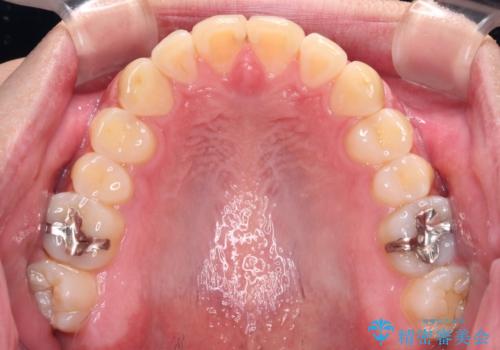

- 上下前歯のデコボコを気にして来院された患者様です。

前歯のデコボコ以外に左側の奥歯の咬み合わせに問題がありましたが、価格を抑え、短期間で気になる前歯を治したいとのことでした。

こちらの患者様は、事前のシミュレーションにより、インビザライン・ライトでは前歯のデコボコを解消しきれないことが分かったため、通常のインビザライン(コンプリヘンシブパッケージ)での治療が必要となりました。

しかし、費用面や期間で悩んでいらっしゃったため、左側臼歯の問題は解決せずに前歯のデコボコのみを改善するシミュレーションを作成し、治療を行うこととしました。

写真より左側臼歯の咬合がタイトではないことが分かりますが、こちらは保定期間に徐々に咬合させていくこととしました。